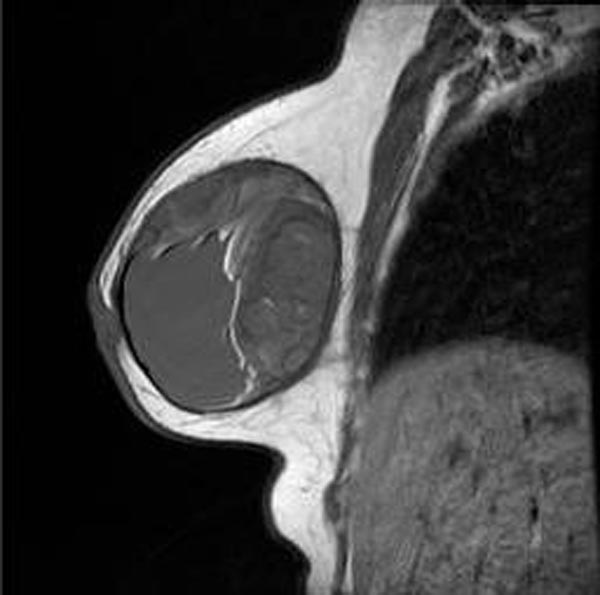

Breast implant ruptured